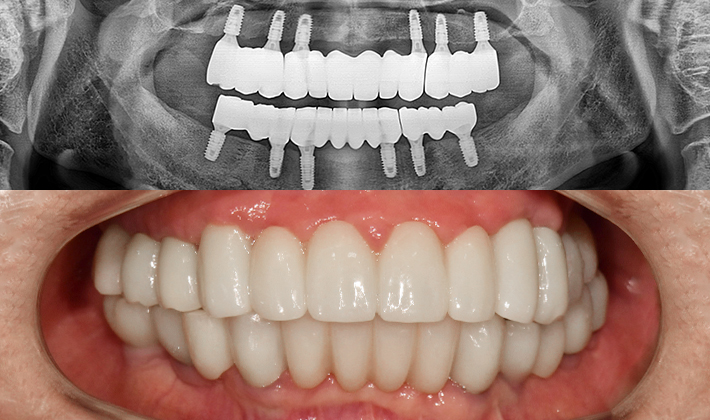

5060 시니어 임플란트

건강하고 오래가는 시니어 임플란트,

치료 사례부터 남다릅니다.

before

after

※ 위 임상사진은 동일조건으로 촬영되었으며, 사진에 대한 별도의 조작이 처리되지 않았습니다.

※ 위 임상사진 및 포트레이트는 환자와의 포괄적인 초상권 계약 이후 사용하고 있습니다.

※ 수술 및 치료과정에서 부작용이 발생할 수 있으므로 충분한 상담과 신중한 판단이 요구됩니다.

실제 치료 사례

수많은 환자들이 고민 끝에 선택한 치료,

그리고 그 후의 놀라운 변화

- ※ 위 임상사진은 365서울원탑치과에서 진료를 시작하고 마친 동일한 환자의 사진입니다.

- ※ 위 임상사진은 동일한 장소에서 동일한 조건으로 촬영되었으며, 사진에 대한 별도의 조작이 처리되지 않았습니다.

- ※ 수술 및 치료 과정에서 부작용이 발생할 수 있으므로 의료진과의 충분한 상담과 신중한 판단이 요구됩니다.